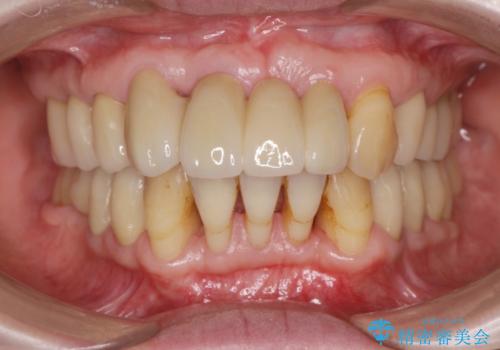

[メタルフリー] 虫歯・銀歯だらけの口腔内を全顎治療

![[メタルフリー] 虫歯・銀歯だらけの口腔内を全顎治療の症例 治療後](https://seimitsushinbi.jp/wp/wp-content/uploads/2025/03/530cf6cca6451bc106a9fb69dd58908a-500x350.jpg?v=1741918343)